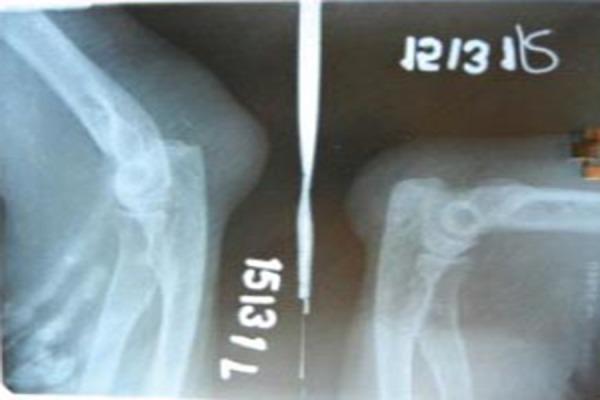

A 42-year-old female patient is presented with golf ball sized painless swellings in the posterior aspect of her elbows. Elbow joints were clinically normal except for restriction of terminal flexion. X-ray showed mild erosion at the tip of olecranon. Excision biopsy of the swelling showed positive birefringent calcium pyrophosphate dehydrate crystals on the inner wall of the specimen on polarized light microscopy.

一名42岁女性患者,双侧肘部后方出现高尔夫球大小的无痛性肿胀。除终末屈曲受限外,肘关节临床检查正常。X线显示鹰嘴尖端轻度侵蚀。肿胀部位的切除活检在偏振光显微镜下显示标本内壁有阳性双折射焦磷酸钙脱水晶体。